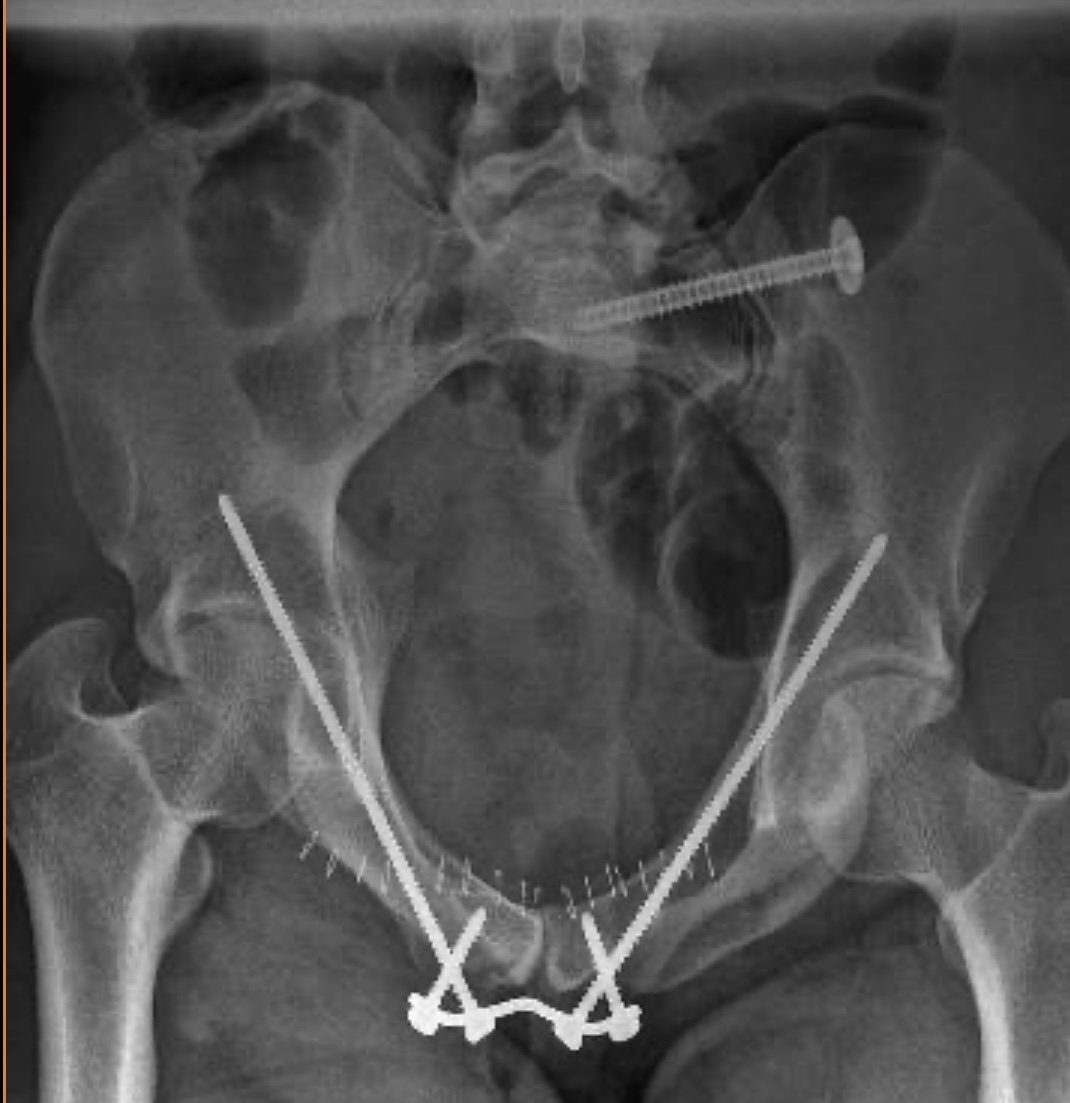

Fractures of the pelvis or hip socket

Pelvic and acetabular injuries require precision and expertise. My approach ensures optimal outcomes, even in the most complex cases.